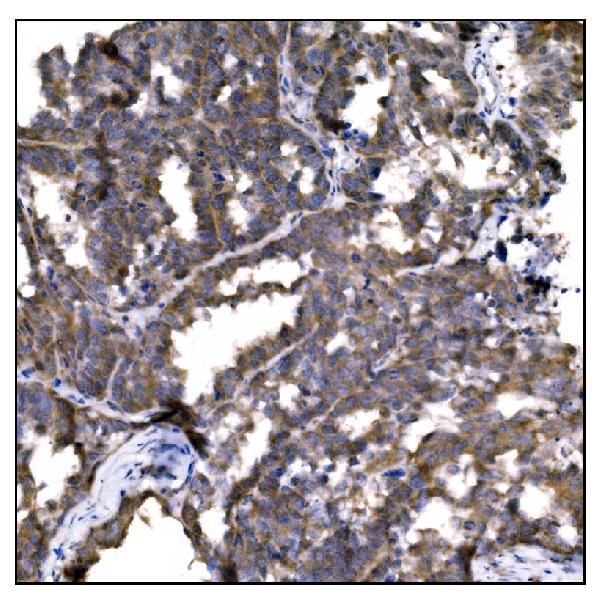

Caspase-8, Monoclonal Antibody (Cat# AAA30210)

Caspase-8, Polyclonal Antibody (Cat# AAA10948)